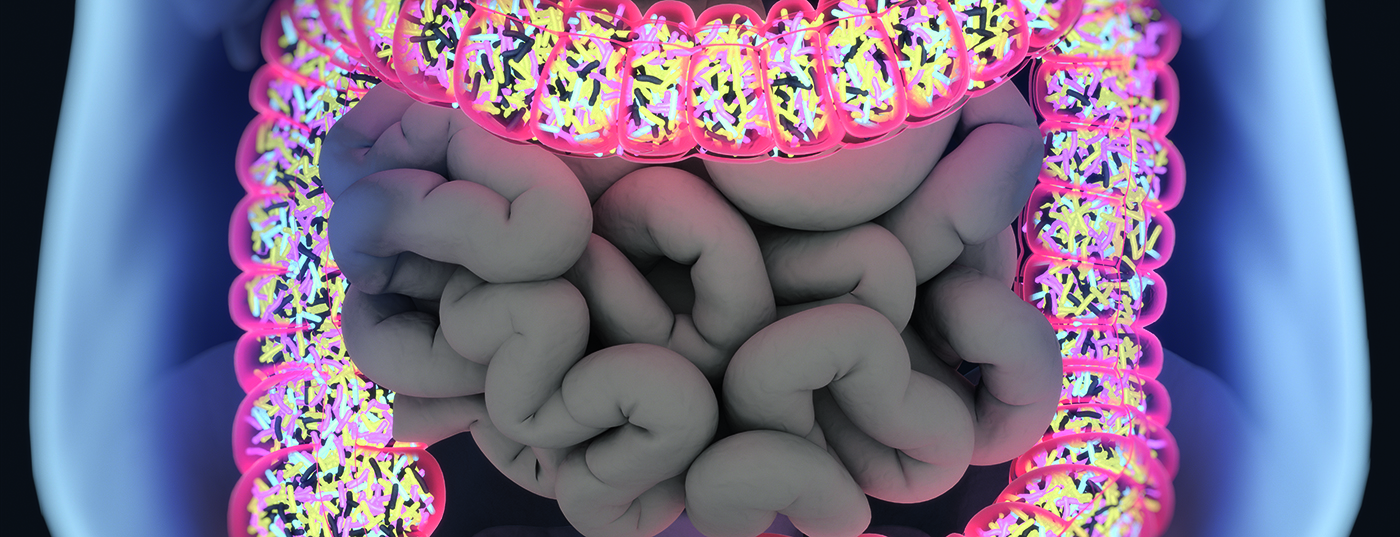

Forschende der ETH Zürich, des Inselspitals und der Universität Bern statten Darmbakterien mit einer Datenlogger-Funktion aus und überwachen damit, welche Gene in den Bakterien aktiv sind. Die Mikroorganismen sollen dereinst auf nicht-invasive Weise Krankheiten diagnostizieren und die Gesundheitsauswirkungen einer Diät erfassen.